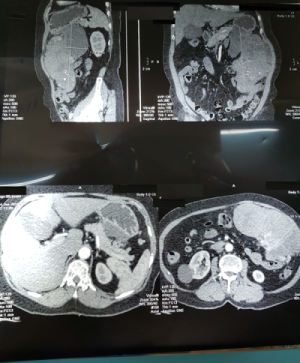

Ngỡ bụng to do tăng cân, người phụ nữ suýt chết vì khối u khủng ảnh 1Kết quả CT SCAN cho thấy hình ảnh khối u rất lớn ở vùng bụng bệnh nhân

Ngay ở bước thăm khám lâm sàng, các bác sĩ tại trung tâm đã ghi nhận một khối u lớn, ấn không đau, khu trú ở vùng hạ sườn trái. Kết quả siêu âm cũng cho thấy một khối u kích thước lớn, chưa rõ bản chất. Bên cạnh đó, kết quả CT scan khảo sát vùng bụng phát hiện khối u mô đệm thành dạ dày, choán chỗ toàn bộ vùng hạ sườn trái, có đường kính lớn nhất lên tới 20 cm.